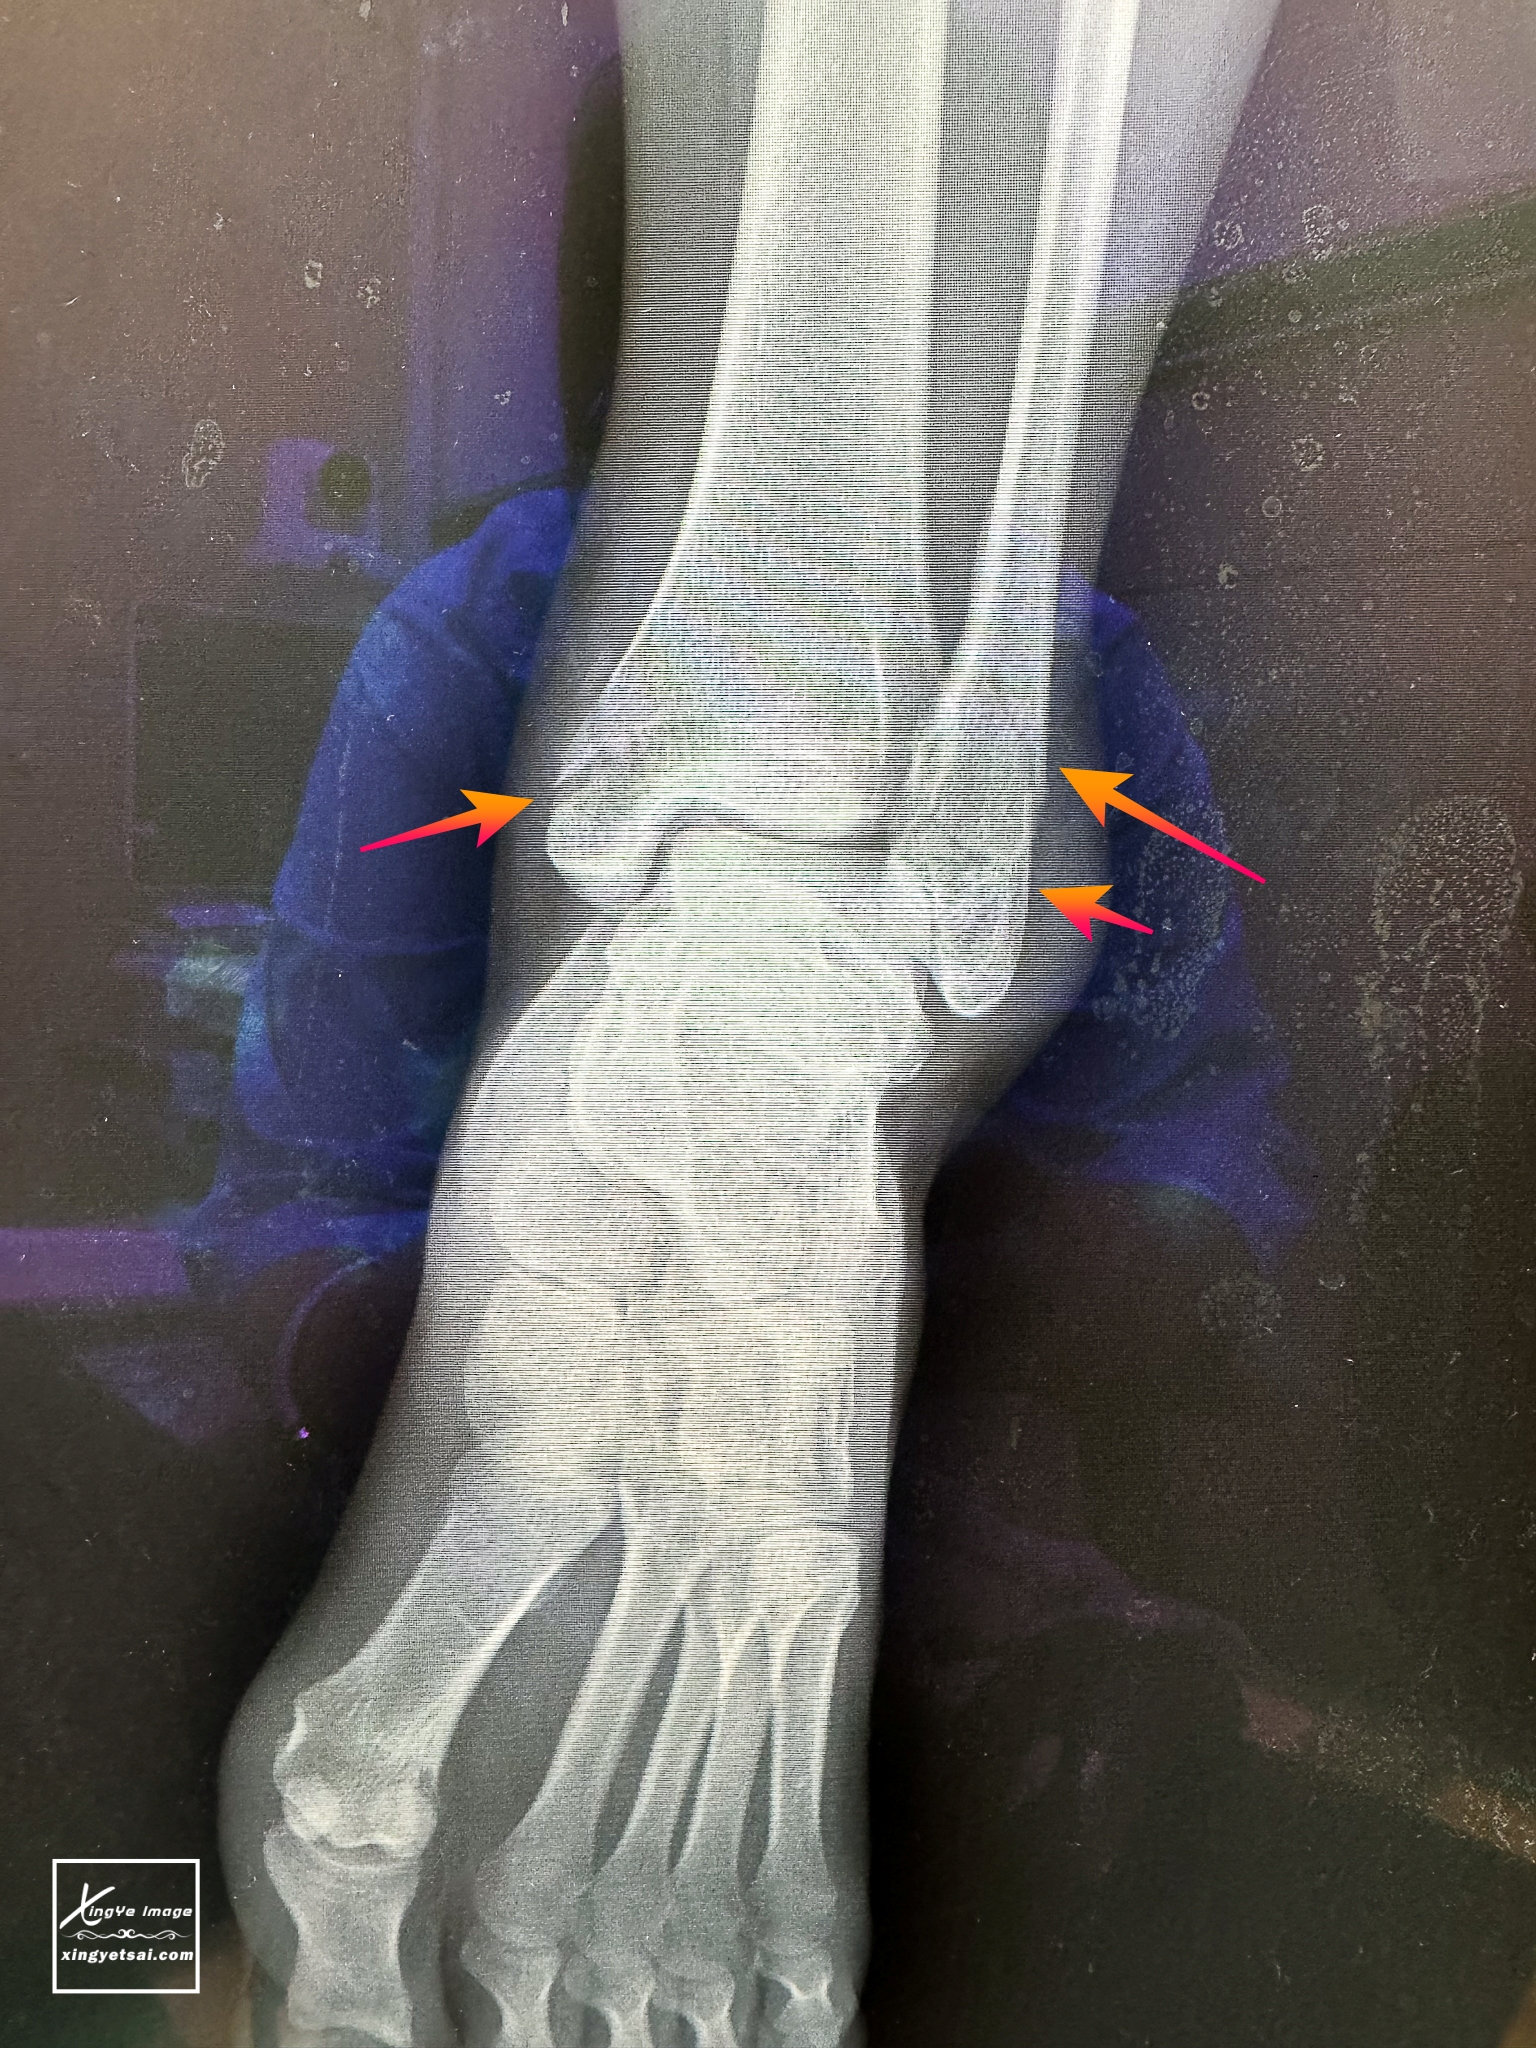

在急診照了X光,左踝關節三踝骨骨折,醫生說傷的挺嚴重,因為左踝關節的左側、右側與後踝都裂了。急診骨科醫師評估需開刀行內固定,自費鈦合金鋼板兩片(一根骨頭需一片),光自費兩片鋼板耗材費用NT$111700,別吃驚,這已經是最便宜的了,以前沒特別在意,竟不知道原來骨傷這麼貴

▲三踝骨折:三踝骨折是一種踝關節的骨折,涉及外踝、內踝和後踝,簡單來說是指腳踝處同時發生內、外、後踝三處都骨折

▲烏梅其中一處骨折斷裂較嚴重,達到個人保險裡「完全性骨折」的理賠